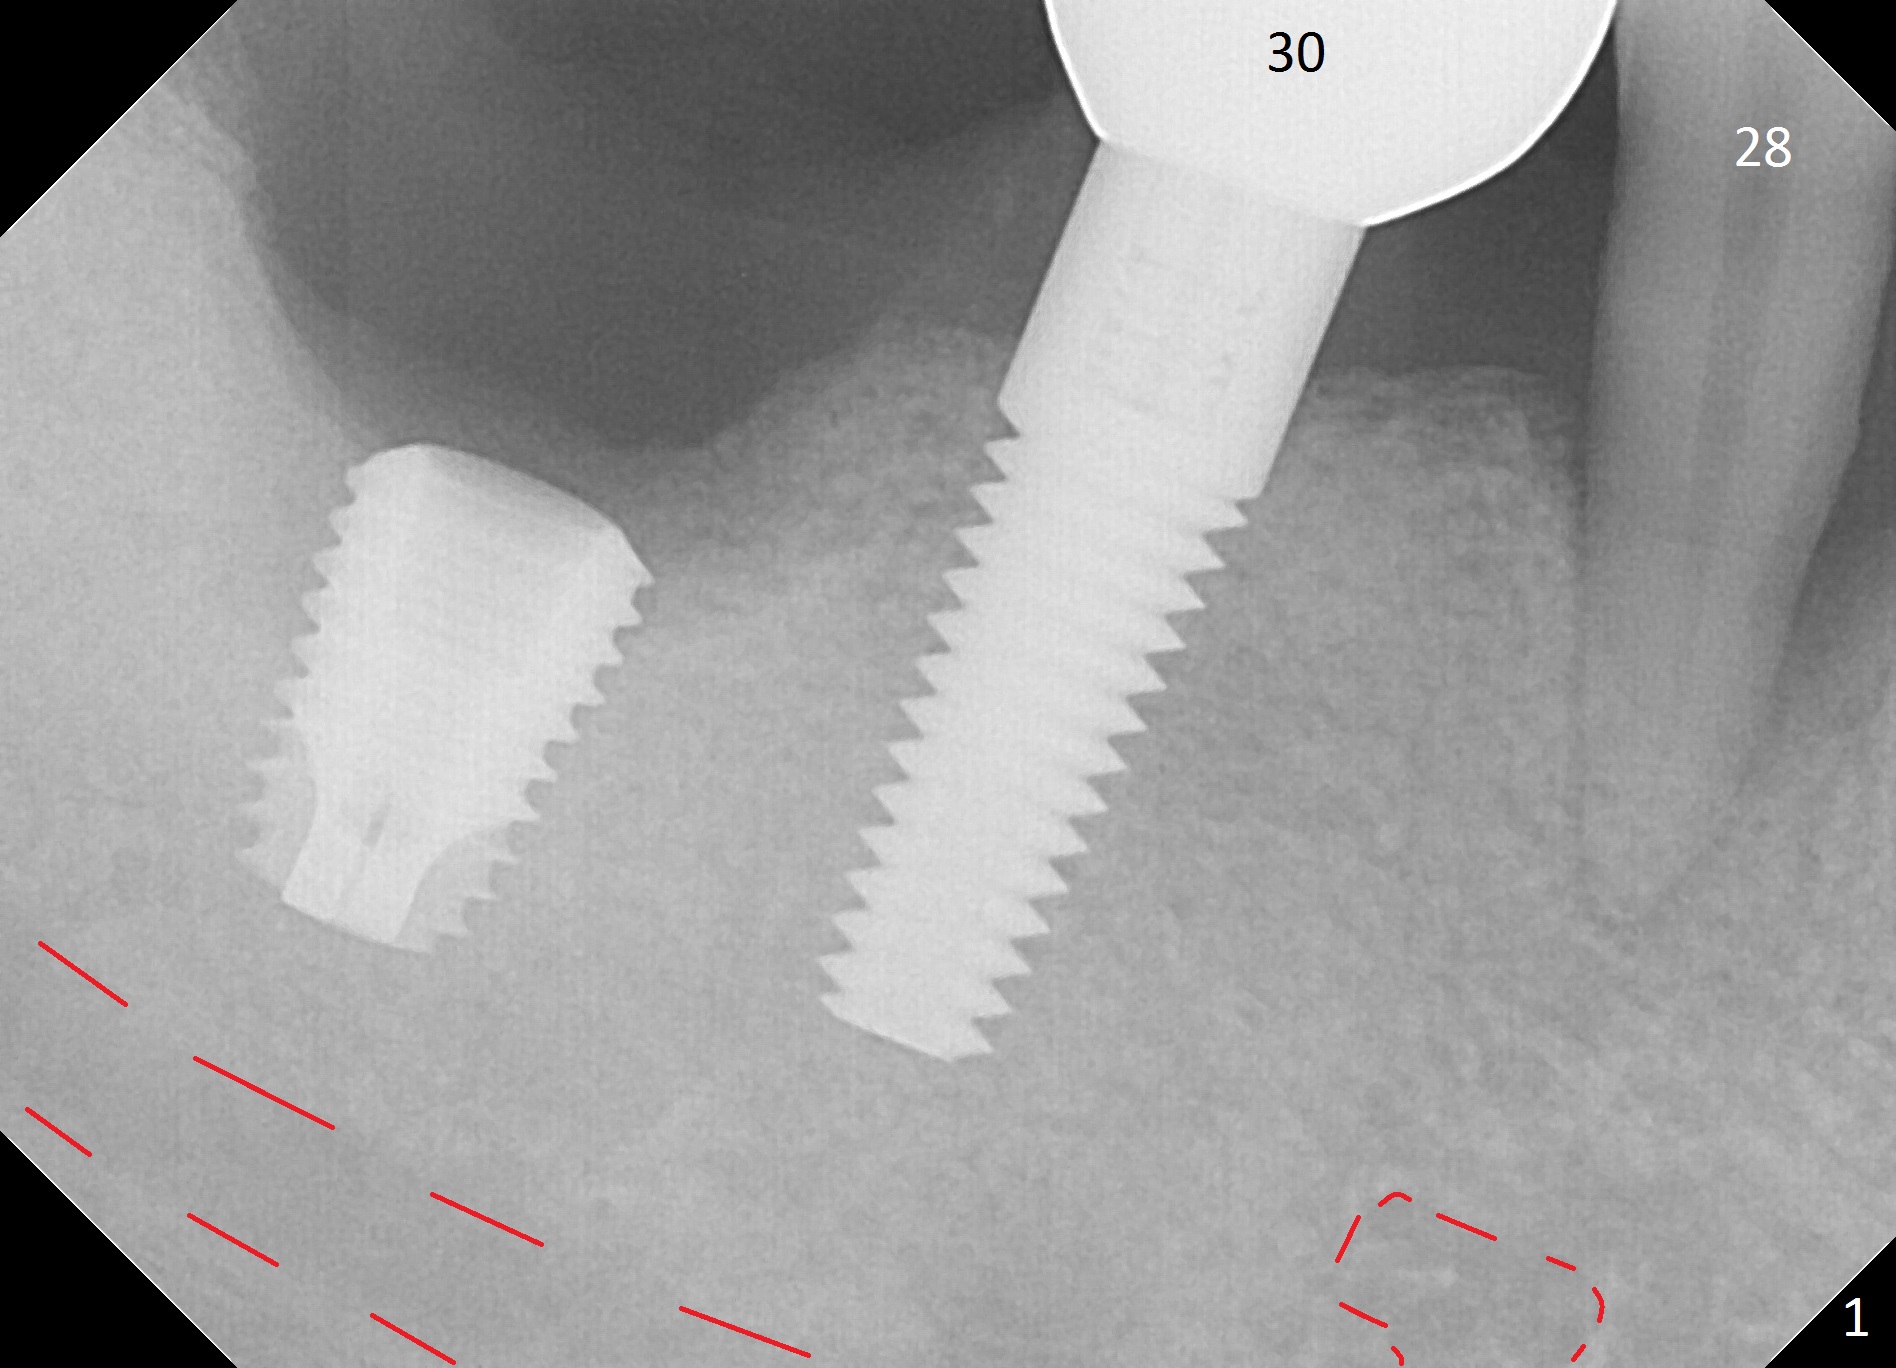

A 44-year-old man will return for #28 extraction and immediate implant 2-3 months after removal of the implant at #31 (Fig.1). After Clindamycin treatment, start osteotomy in the middle of the lingual wall of the socket (Fig.2,3 red line) with 1.6 mm for 13 mm (from oblique to straight). Take PA to determine clearance from the Mental Loop (Fig.1 red dashed line). If the trajectory is right, use 3.3 mm Magic Drill (MD) and possibly 3.8 mm one for short distance, since the bone density near the socket 700 units, while apically 100 units. Or use a 4x11 mm IBS dummy implant instead of 3.8 mm MD. An angled abutment may be used (Fig.2). Also prepare UF in case the gingiva is thick.